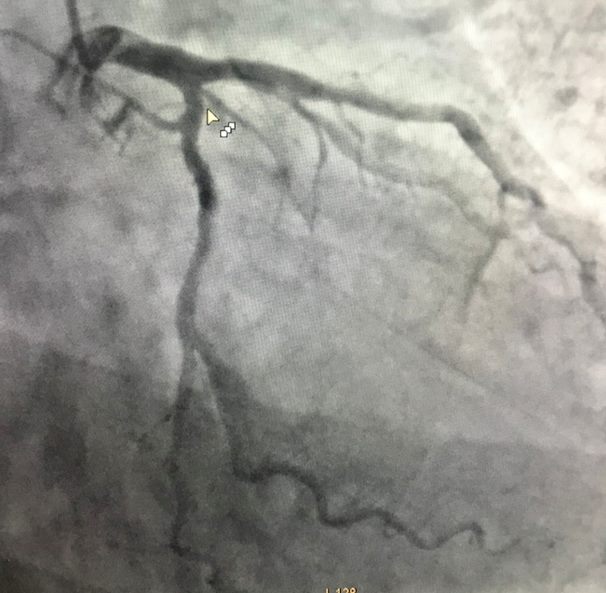

李先生心电图结果

众所周知,南非国旗的旗面中央是一横Y型三色条,而在心电图中,旗面中央Y型三色条可分别对应于心电图中的I导联、aVL导联、III导联、V2导联。当存在对角支闭塞的时候,可以在这四个导联中出现ST段异常。

根据心电图结果,提示李先生为急性心肌梗死,考虑为对角支病变。

完善检查后,杨海涛副主任医师给予患者冠心病二级预防药物。效果一般,患者仍有症状。进一步为李先生冠脉造影显示:第一对角支80-90%狭窄。